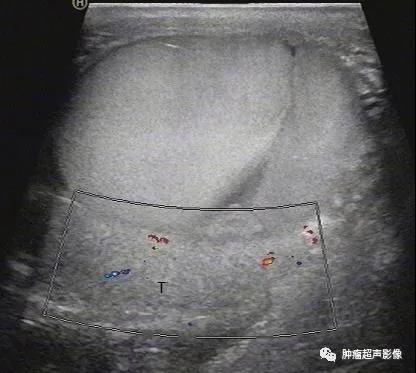

继续扫查可见睾丸(T)被压迫在一边,这其实是一个血性睾丸鞘膜腔积液

穿刺后睾丸鞘膜腔血性积液:充满密集点状回声